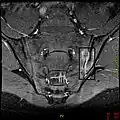

If these criteria still do not give a compelling diagnosis magnetic resonance imaging (MRI) may be useful.[22][24] MRI can show inflammation of the sacroiliac joint.